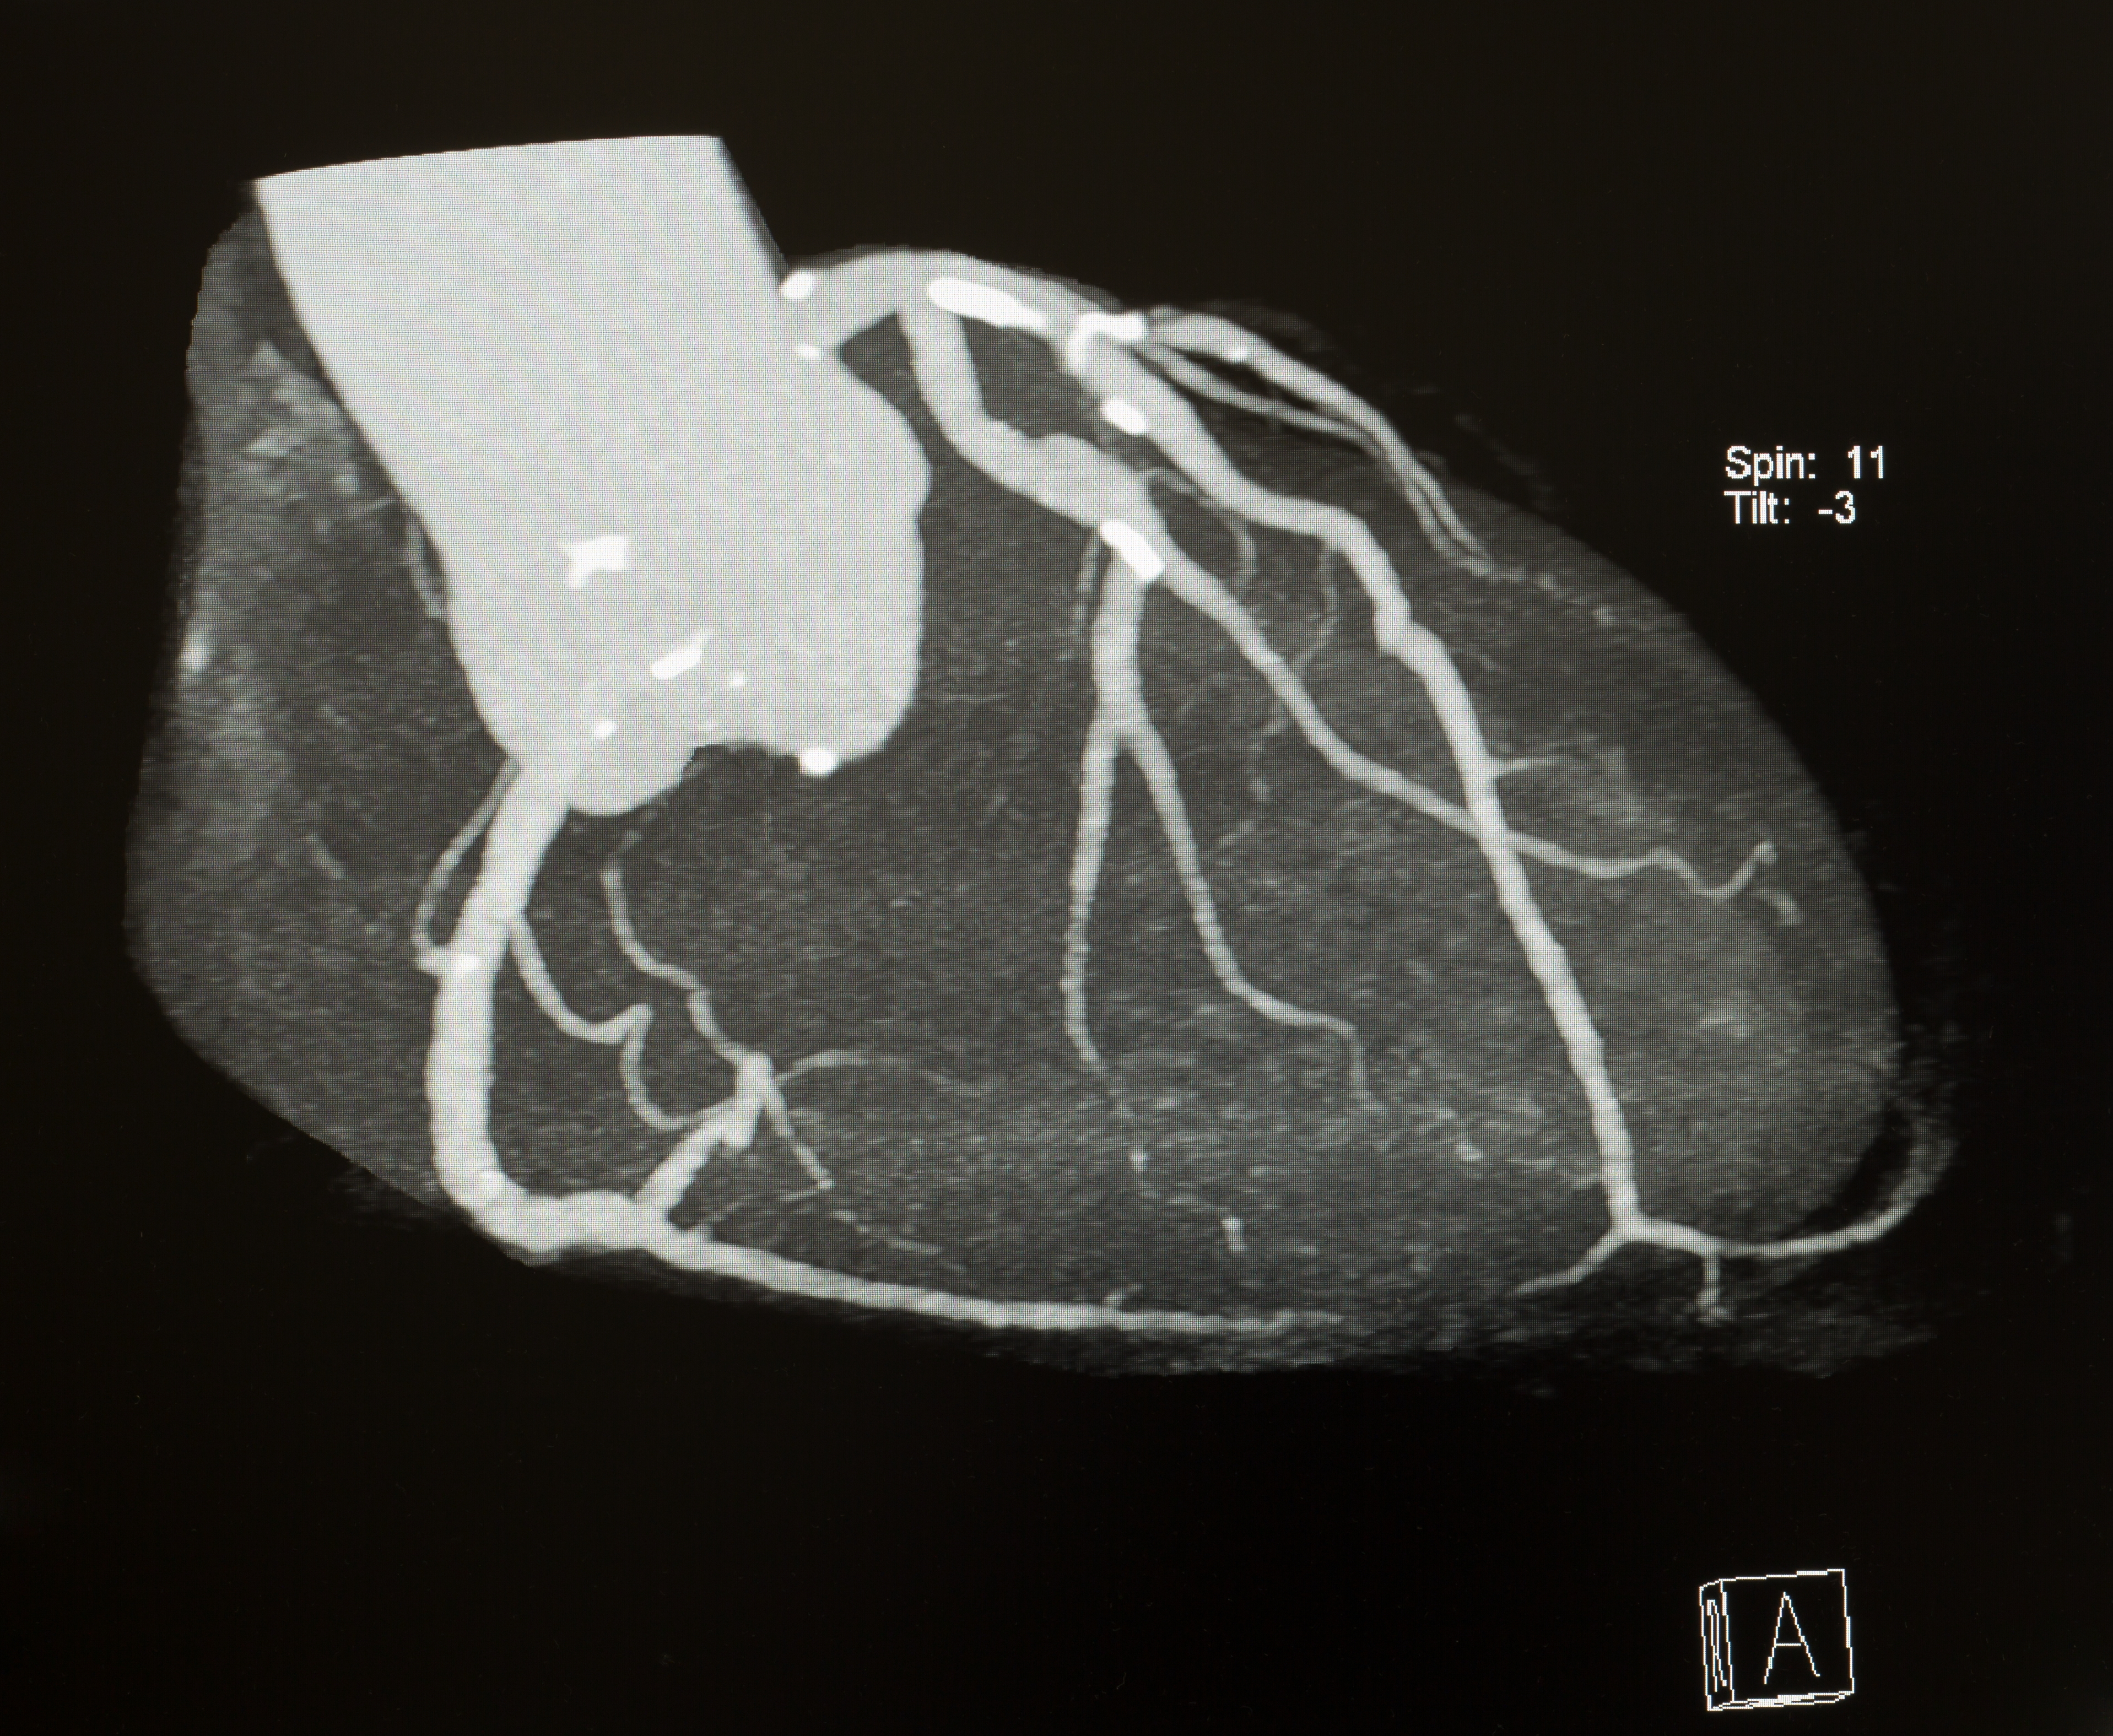

A 3D reconstruction image of cardiac CT, the brightest white is a calcified plaque of blood vessels.